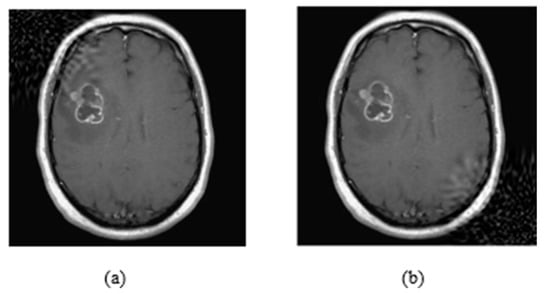

According to the results, CT-Scan was the least robust modality, as the accuracy of the models was reduced almost by 50%. This is very interesting, as COVID-19 detection using CT-Scans should have been the most robust problem because it has only two classes. Even with the smallest perturbation, MobileNetV2 was decreased by 12.2% in terms of accuracy (Figure 9). The CT-Scan modality should be further investigated to draw safe conclusions. The problem of brain tumor classification was the most difficult one and therefore the performance of the models, even with clean images, was low. However, the models did not lose significant accuracy with an imperceptible perturbation. On X-rays, accuracy decreases significantly when we increase the embedding strength, or we insert a lot of information.

Figure 9.

(a) Clean Image, (b) Attacked image (L-Bit = 100, Embedding strength = 50).